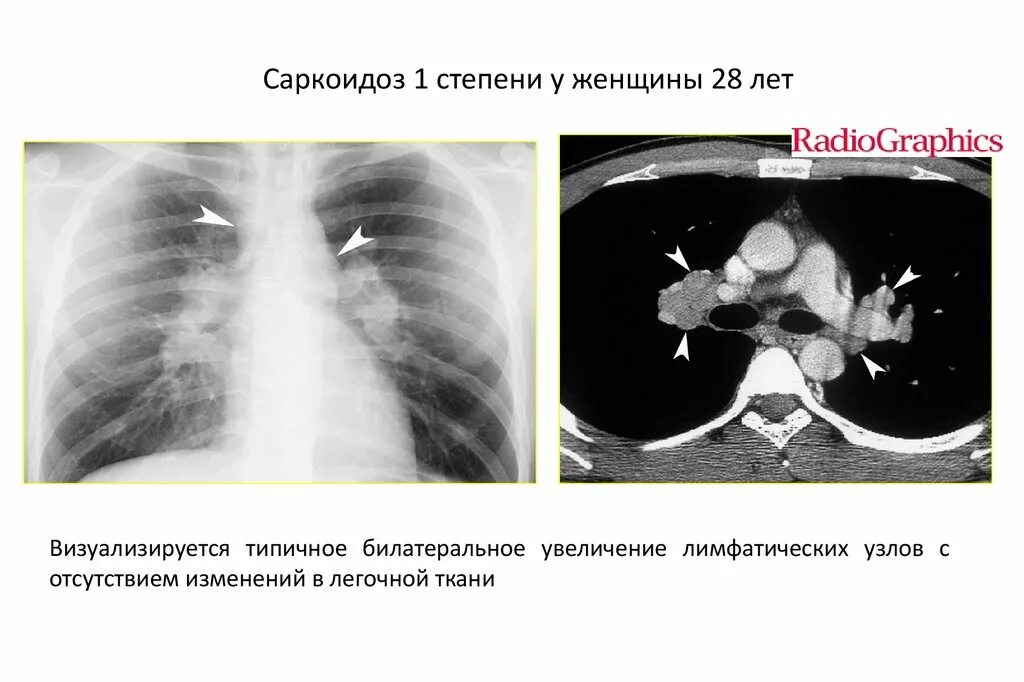

Саркоидоз 1